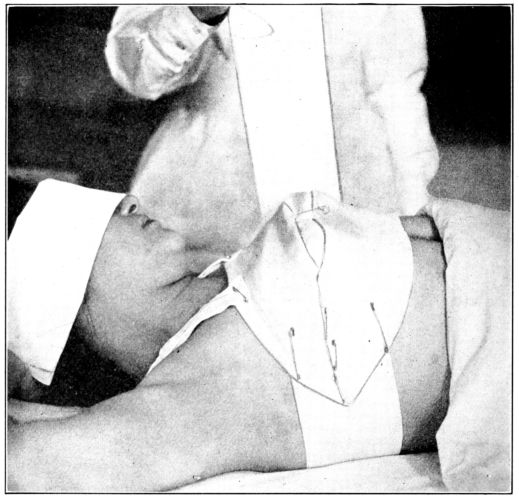

| 125. | Y binder applied | 346 |

| 126. | The same seen from the other side | 347 |